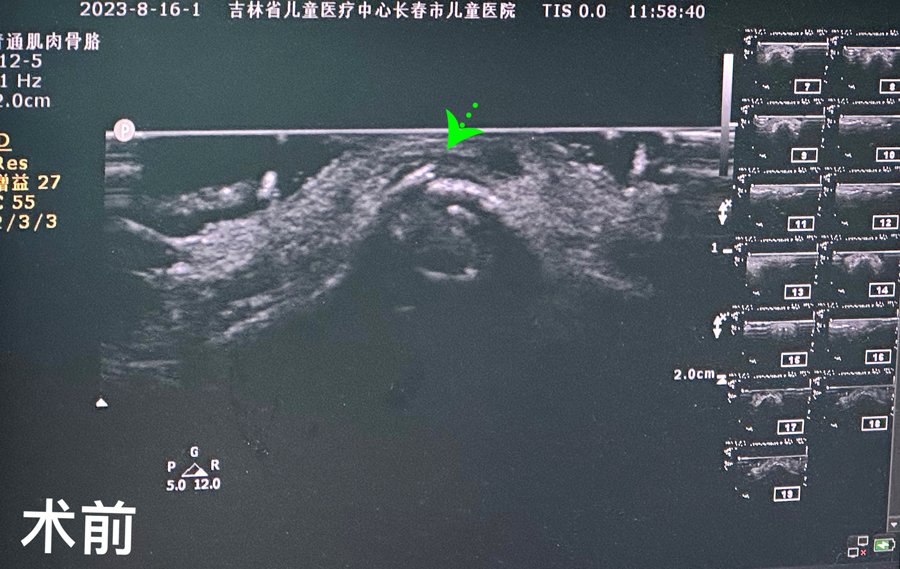

8月15日,彬彬家长在辗转多家医院后,听说啪啪网 有鼻骨骨折复位新技术,立即带彬彬赶到医院。此时,距离彬彬鼻骨骨折已经过去一周了。就诊时,彬彬鼻部肿胀已经消退了,能看到他的鼻梁是向左侧偏曲的,妈妈特别希望孩子的鼻梁能恢复到从前高挺、居中的状态。国家儿童医学中心、北京儿童医院耳鼻喉头颈外科常驻专家、啪啪网 副院长张薇,啪啪网 耳鼻喉科主任李莉萍为其进行鼻部检查,并结合鼻骨CT全面评估后,决定采用超声引导下鼻骨骨折复位术,以实现精准复位,使彬彬的面容不受影响。8月16日,张薇副院长、李莉萍主任及手术室、麻醉科医护人员组成手术团队,为彬彬进行手术。术中,医生在超声引导下应用复位器对游离骨片进行复位调节,使错位的鼻骨重新连续。10分钟后,手术顺利完成,复位后的鼻子外观无畸形。术后,彬彬接受抗感染治疗48小时,情况稳定,顺利出院。

相比较传统凭经验及手感的鼻骨复位术,超声引导下的手术复位能更精准定位到损伤部位,如医生的“透视眼”,实现手术可视化,使医生在术中可准确看到鼻骨断端的对合情况,在“精准、微创、美观”上得到极大优化和提升。患儿无伤口、恢复快。术前和术后鼻骨错位及对合情况B超均有图片准确显示,让家长也能看明白,患儿和家长的心理负担明显减轻不少,改善了就医体验。